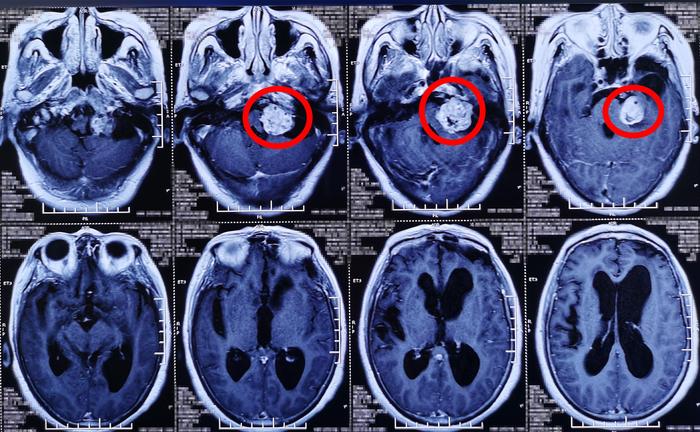

学员进行了读片及鉴别诊断,指出桥小脑角区肿瘤需考虑脑膜瘤,听神经瘤